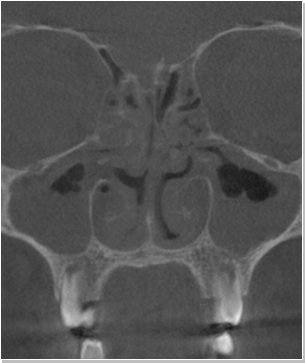

비중격만곡증

비중격 연장술 후 비중격만곡증 재수술 가능할까요?비중격만곡증 질환 수술만 했을 경우 비중격만곡증 재수술이 가능합니...

코는 미용적인 부분 그리고 기능적인 부분을 따로 나누어 생각해야 한다. 하지만 나누어 생각해야 한다고 해서 각각의 부...